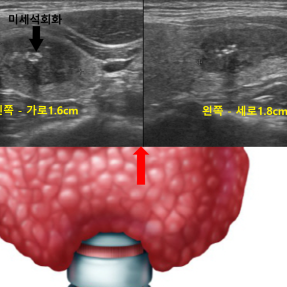

Thyroid Clinic

갑상선 클리닉